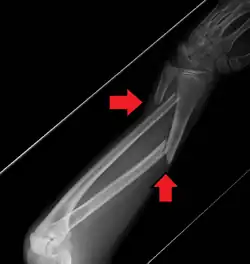

Midshaft fracture of the radius and ulna

A fracture of the forearm can be classified as to whether it involves only the ulna (ulnar fracture), only the radius (radius fracture), or both radioulnar fracture.